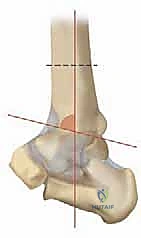

* المنظر الأمامي الخلفي (AP View): لتقييم المسافة المفصلية وتحديد زاوية سطح الساق (Tibial Anterior Surface Angle - TAS).

* منظر سالتزمان (Saltzman View): وهو منظر إشعاعي متخصص جداً لتقييم محاذاة الكعب الخلفي بالنسبة لمحور الساق، وهو أمر حاسم في التخطيط الجراحي.

التخطيط الجراحي: دقة المليمتر مع الدكتور محمد هطيف

النجاح في جراحة قطع العظم لا يحدث في غرفة العمليات، بل في مرحلة التخطيط التي تسبقها. يستخدم الدكتور هطيف برمجيات حاسوبية متقدمة لتحليل صور الأشعة وحساب زوايا التصحيح المطلوبة بدقة متناهية.